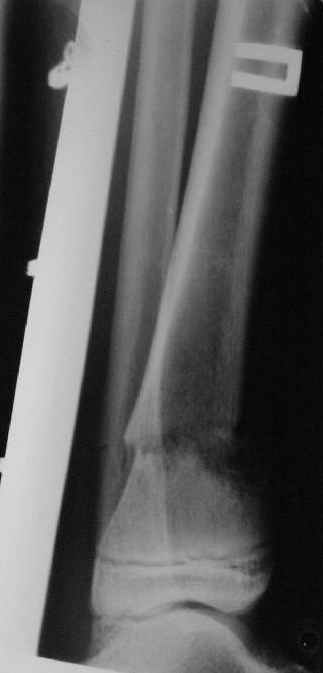

A>> Перелом костей н\3 правой голени со смещением.

AVM> Это от 13.10.04? А это близкие к первичным снимки?

Есть даже тень периостальной костной мозоли и сросшийся перелом

малоберцовой кости.

Это сросшийся перелом малоберцовой кости. И ложный сустав

н\3 б\берцовой кости.

Так как речь зашла непосредственно о травме, см этапные

снимки. Как все было

Первичные